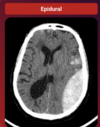

40

Achado?

HSA